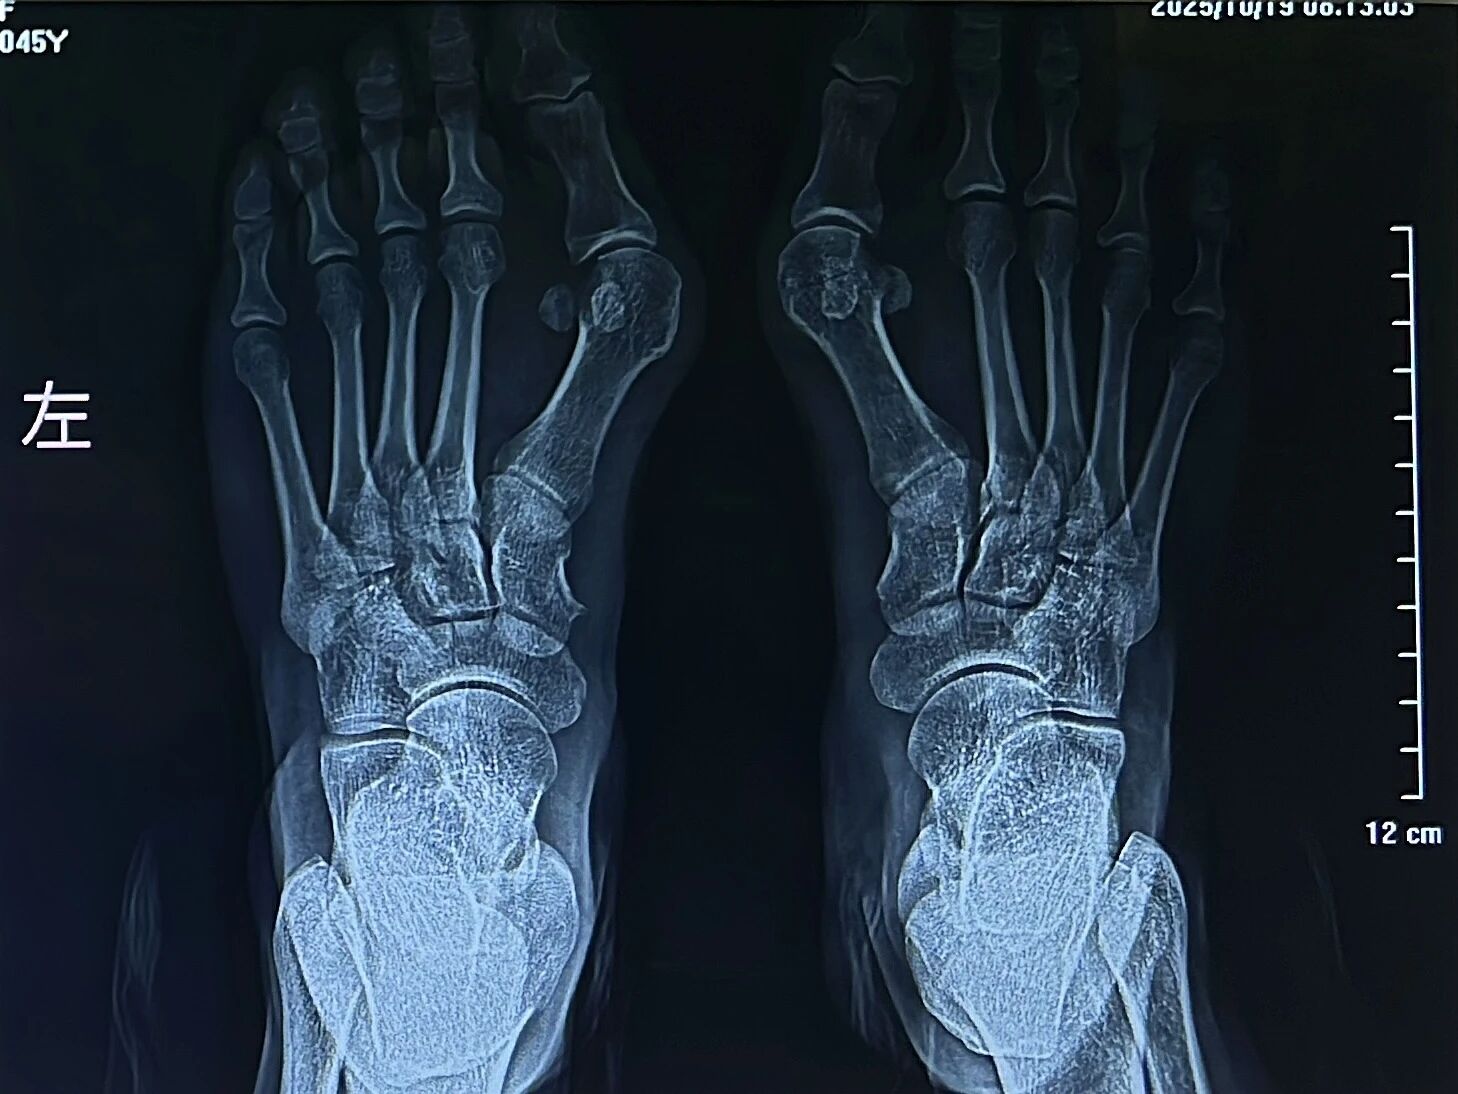

▲术前

▲术后

此次诊疗活动不仅展现了国家级医疗技术的突破性进展,体现了周口人合医院"社会满意、百姓放心"的办院宗旨,更为周边市民骨科疾病诊疗树立了新标杆。